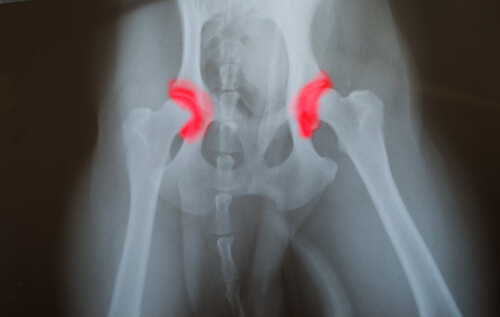

Un ejemplo es la displasia de cadera, un mal caracterizado por los desligamientos y mal funcionamiento de la cadera y sus rótulas, muy común en las razas grandes como los pastores alemanes y la mayoría de los dogos.